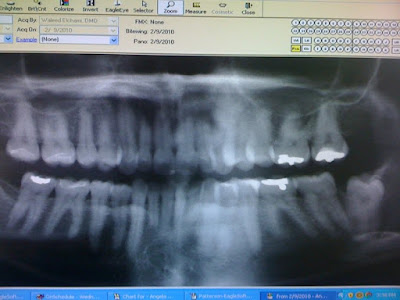

Earlier today I got to visit my dentist and take care of my chompers which I love getting my teeth cleaned… just like people like getting needles to skin for ink I love those needles to gums for teeth. I am not sure why but I really enjoy it for reals… it’s like a tooth spa. While I was there my dr. let me take a phone pict. of my mouth x-ray! They think I am funny there how excited I get over teeth.